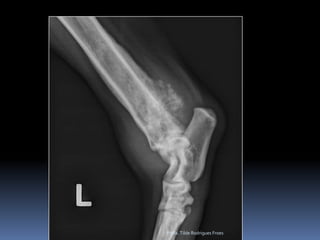

Animal: Mike, canino Canino, macho, 11 anos, ROTTHX: Claudicação posteriores    Déficit de propriocepçãoProfa. Tilde Rodrigues Froes

Animal: Mike, caninoCanino, macho, 11 anos, ROTTHX: Claudicação posteriores Déficit de propriocepçãoProfa. Tilde Rodrigues Froes